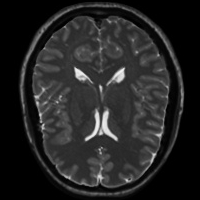

4.4 Qualitative Evaluation

In Figure 5 we analyze the prediction quality of our and compared approaches in a qualitative way. Considering modality propagation in MRI, we see that usage of uncertainty-aware patch invariance (UAPI) gives a better detailed weighting of the cerebrospinal fluid in the middle of the brain. In general, employing patch invariance yields better preservation of fine structures. This observation also applies to accelerated MRI enhancement. In particular, CUT and UAPI provide comparatively sharper knee images with more high-frequency details than the other methods.